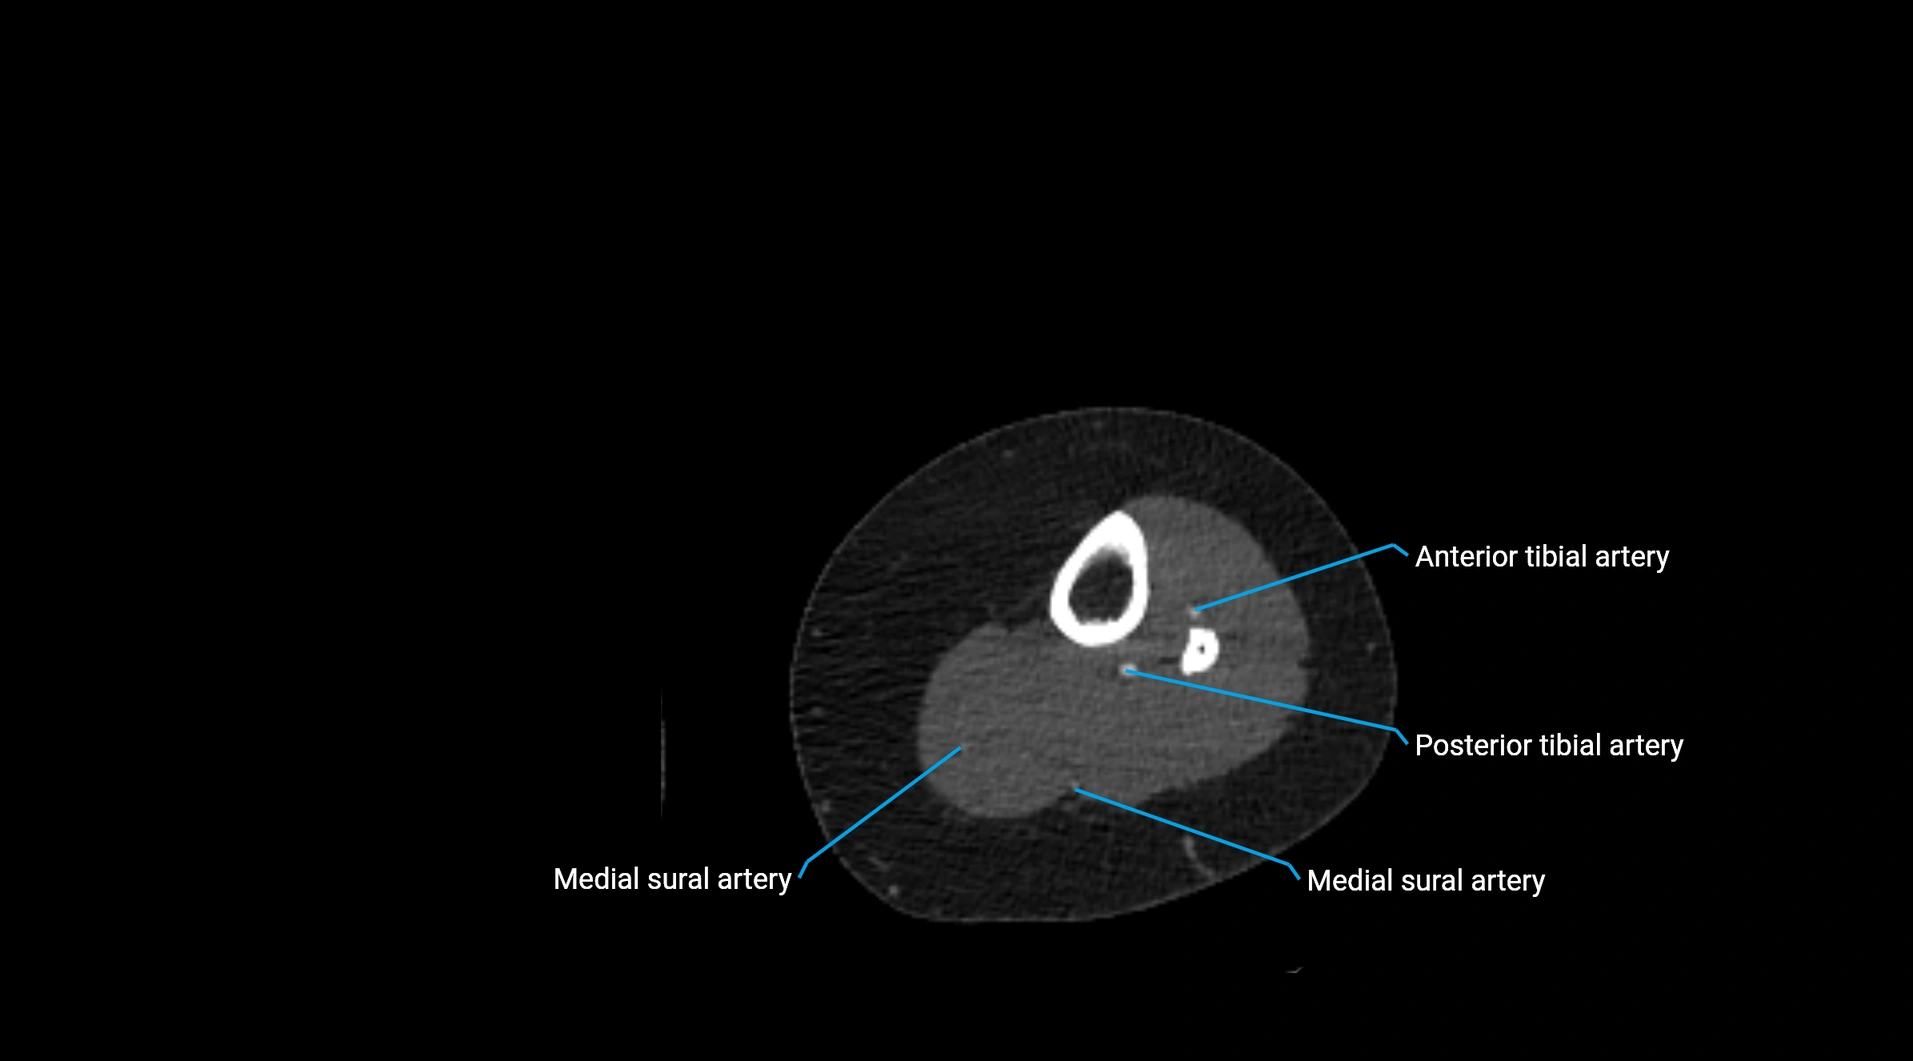

CT Appearance

Non-contrast CT:

• Appears as a tubular soft tissue structure anterior to vertebral bodies

• Calcified atherosclerotic plaques appear as hyperdense foci along the wall

• Useful for screening abdominal aortic aneurysm (AAA) size and mural calcification

Contrast-enhanced CT (CTA):

• Gold standard for abdominal aortic imaging

• Provides excellent detail of lumen, wall, aneurysm, thrombus, and branch vessels

• Multiplanar and 3D reconstructions help in aneurysm measurement, stent graft planning, and dissection evaluation

• Detects acute rupture, traumatic injury, or occlusion with high sensitivity